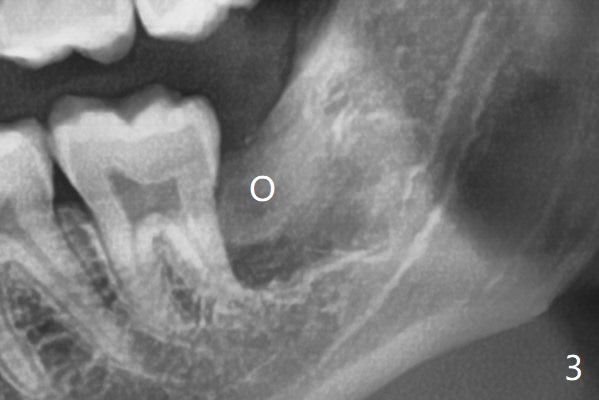

A 22-year-old man, asymptomatic, is going to have #1,16,17 and 32 extracted (Fig.1, fully bony impaction). For the large lower sockets (actually Buccal Impaction), collagen plug is placed in the inferior half, while Bone Cement (Bond Apatite from Augma (Fig.3 A)) and Osteogen plug (O) in the superior half at #32 and 17, respectively.